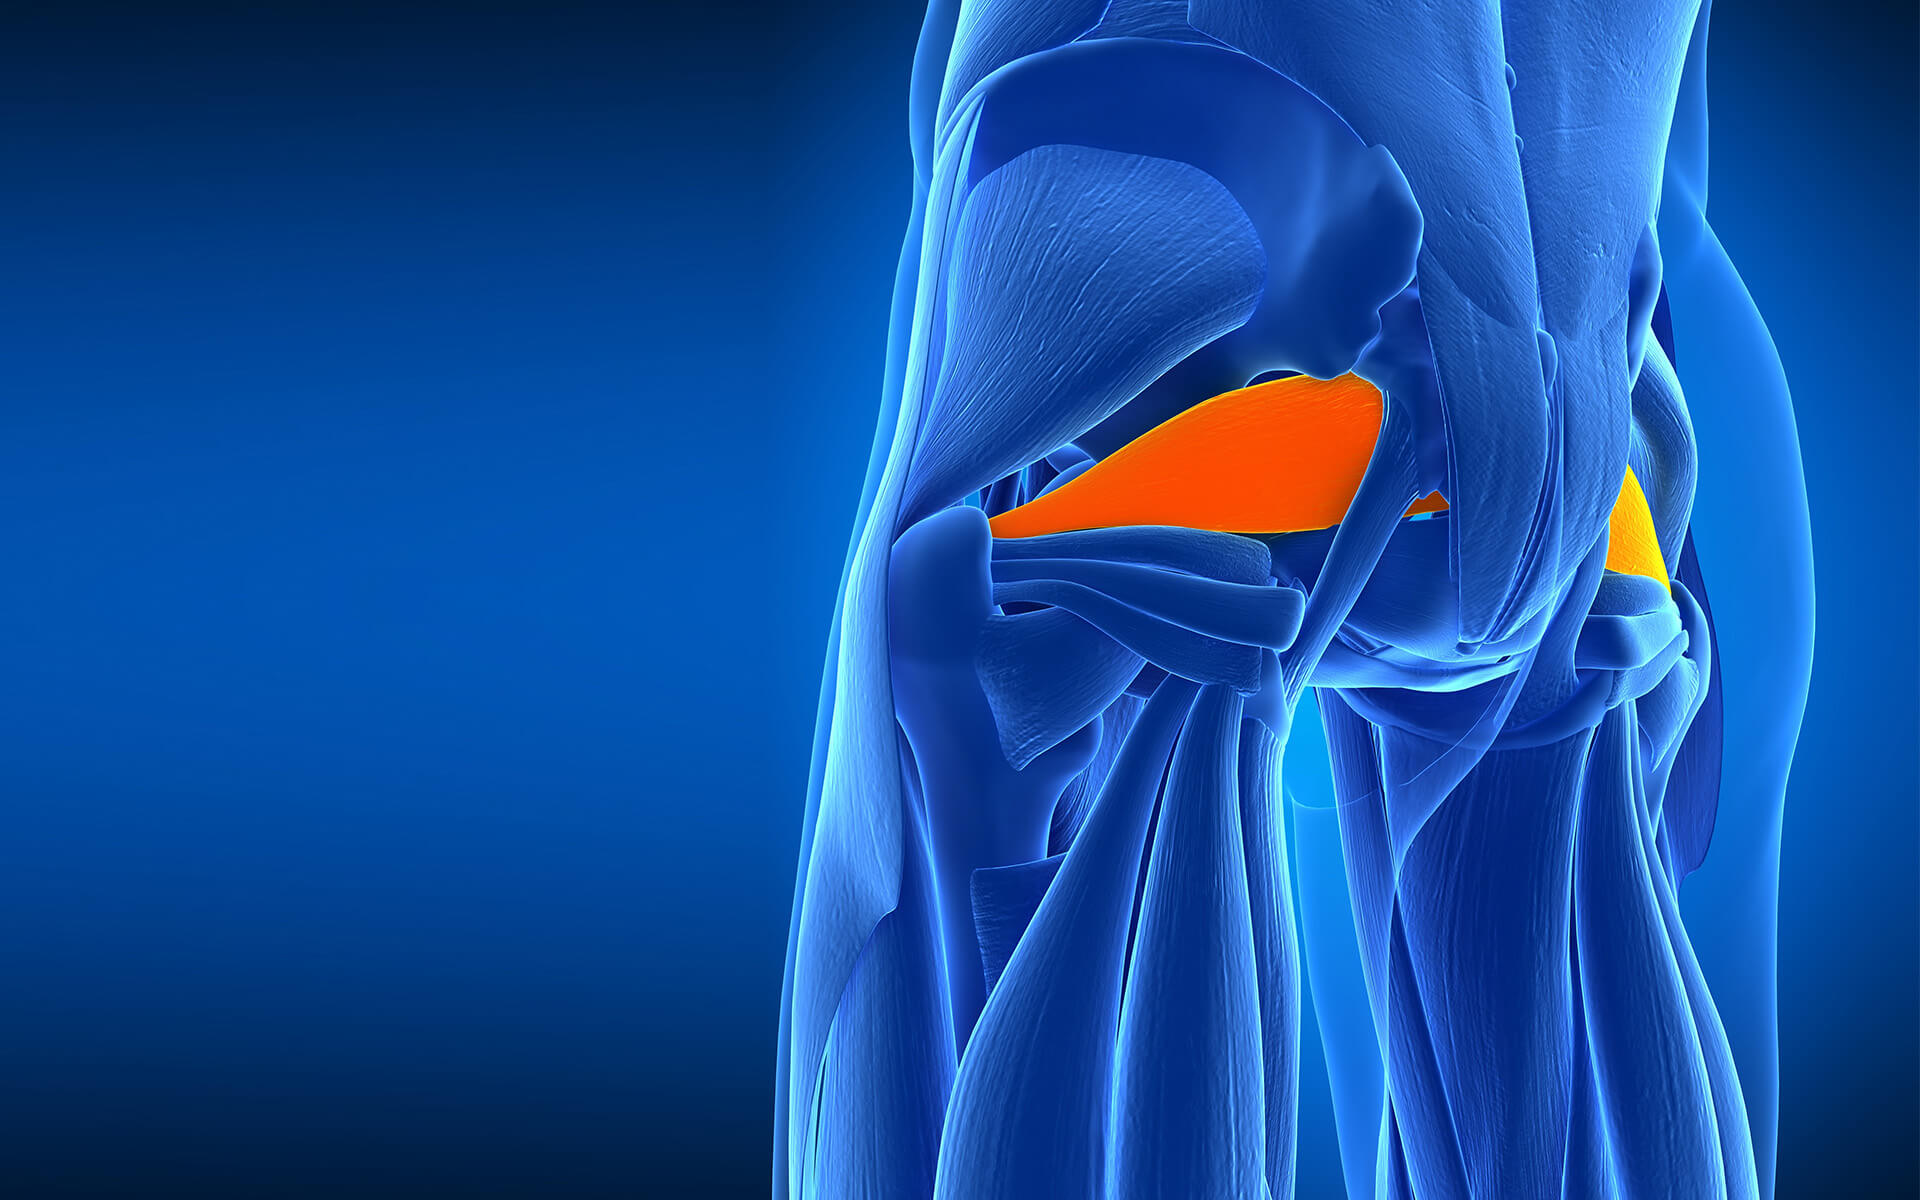

Анатомия мышц: Пириформис